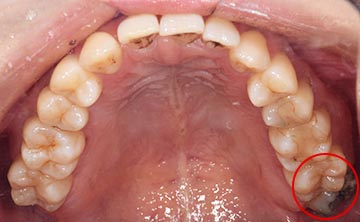

麻布十番歯科で親知らずが真っ直ぐ生えている症例の口腔内写真のイメージ

逆に抜くのが簡単なケースは、真っ直ぐはえている上顎の親知らずです。上顎は下顎よりも骨が柔らかく、かつ根が真っ直ぐになっていることがおおいです。そのため抜くのが簡単な傾向にあります。